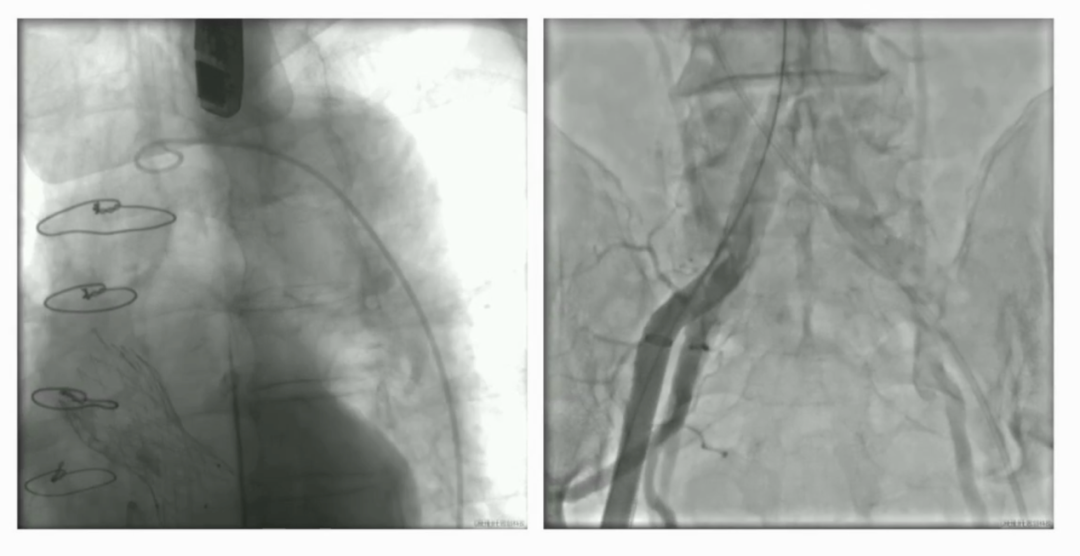

手术直播2:极重度钙化Type 1二叶瓣

本例患者78岁男性,重度AS并合并多瓣膜钙化,PGmax达112mmHg。CT评估提示Type-1二叶瓣,左右融合伴极重度钙化,延伸至升主动脉;瓣环与流出道均有钙化沉积,手术风险高。

经全面评估,最终拟经股入路,采用20/22 mm球囊预扩张后,植入VenusA-L 29mm瓣膜,备用32 mm瓣膜。术后造影与超声评估均显示瓣膜展开理想,无明显反流,手术成功。

小球囊预扩张

20mm球囊预扩张

双平面造影确认植入位置

释放完成

球囊后扩后,超声确认植入位置合适,形态满意,造影未见反流